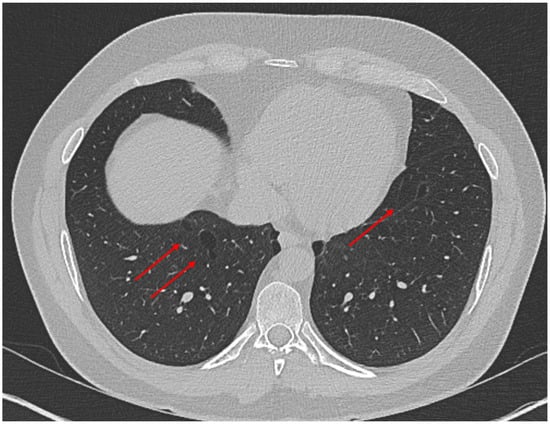

- Hill, D.A.; Ivanovich, J.; Priest, J.R.; Gurnett, C.A.; Dehner, L.P.; Desruisseau, D.; Jarzembowski, J.A.; Wikenheiser-Brokamp, K.A.; Suarez, B.K.; Whelan, A.J.; et al. DICER1 mutations in familial pleuropulmonary blastoma. Science 2009, 325, 965. [Google Scholar] [CrossRef]

- Seki, M.; Yoshida, K.; Shiraishi, Y.; Shimamura, T.; Sato, Y.; Nishimura, R.; Okuno, Y.; Chiba, K.; Tanaka, H.; Kato, K.; et al. Biallelic DICER1 mutations in sporadic pleuropulmonary blastoma. Cancer Res. 2014, 74, 2742–2749. [Google Scholar] [CrossRef] [PubMed]

- Fernández-Martínez, L.; Villegas, J.A.; Santamaría, Í.; Pitiot, A.S.; Alvarado, M.G.; Fernández, S.; Torres, H.; Paredes, Á.; Blay, P.; Balbín, M. Identification of somatic and germ-line DICER1 mutations in pleuropulmonary blastoma, cystic nephroma and rhabdomyosarcoma tumors within a DICER1 syndrome pedigree. BMC Cancer 2017, 17, 146. [Google Scholar] [CrossRef] [PubMed]

- Brenneman, M.; Field, A.; Yang, J.; Williams, G.; Doros, L.; Rossi, C.; Schultz, K.A.; Rosenberg, A.; Ivanovich, J.; Turner, J.; et al. Temporal order of RNase IIIb and loss-of-function mutations during development determines phenotype in pleuropulmonary blastoma/DICER1 syndrome: A unique variant of the two-hit tumor suppression model. F1000Research 2015, 4, 214. [Google Scholar] [CrossRef] [PubMed]